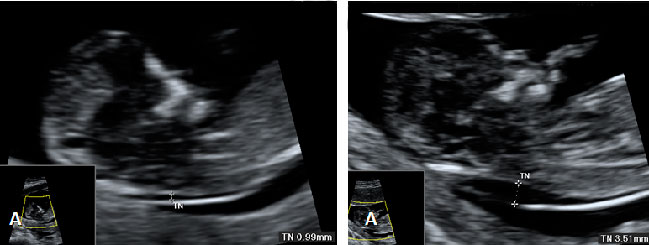

La ecografía de la derecha muestra a un bebé con un cribado positivo que resultó tener un síndrome de Down. La translucencia nucal (o pliegue nucal) por ecografía se ve como un espacio negro en la parte posterior del cuello, acotado por las marcas del ecografista. El bebé de la izquierda tiene una translucencia nucal normal.

Translucencia nucal (TN) normal (A) y patológica (B)